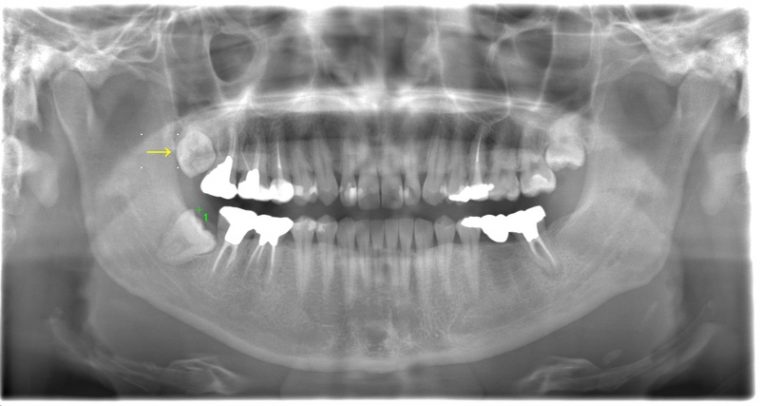

CASE 2

| 主訴 | 左上下親知らず抜きたい |

| 抜歯期間 | 30分 |

| 抜歯費用 | 約2,500円(保険内) 別途CT撮影で3,000円 |

| 抜歯内容 | 左上下の親知らず抜歯 |